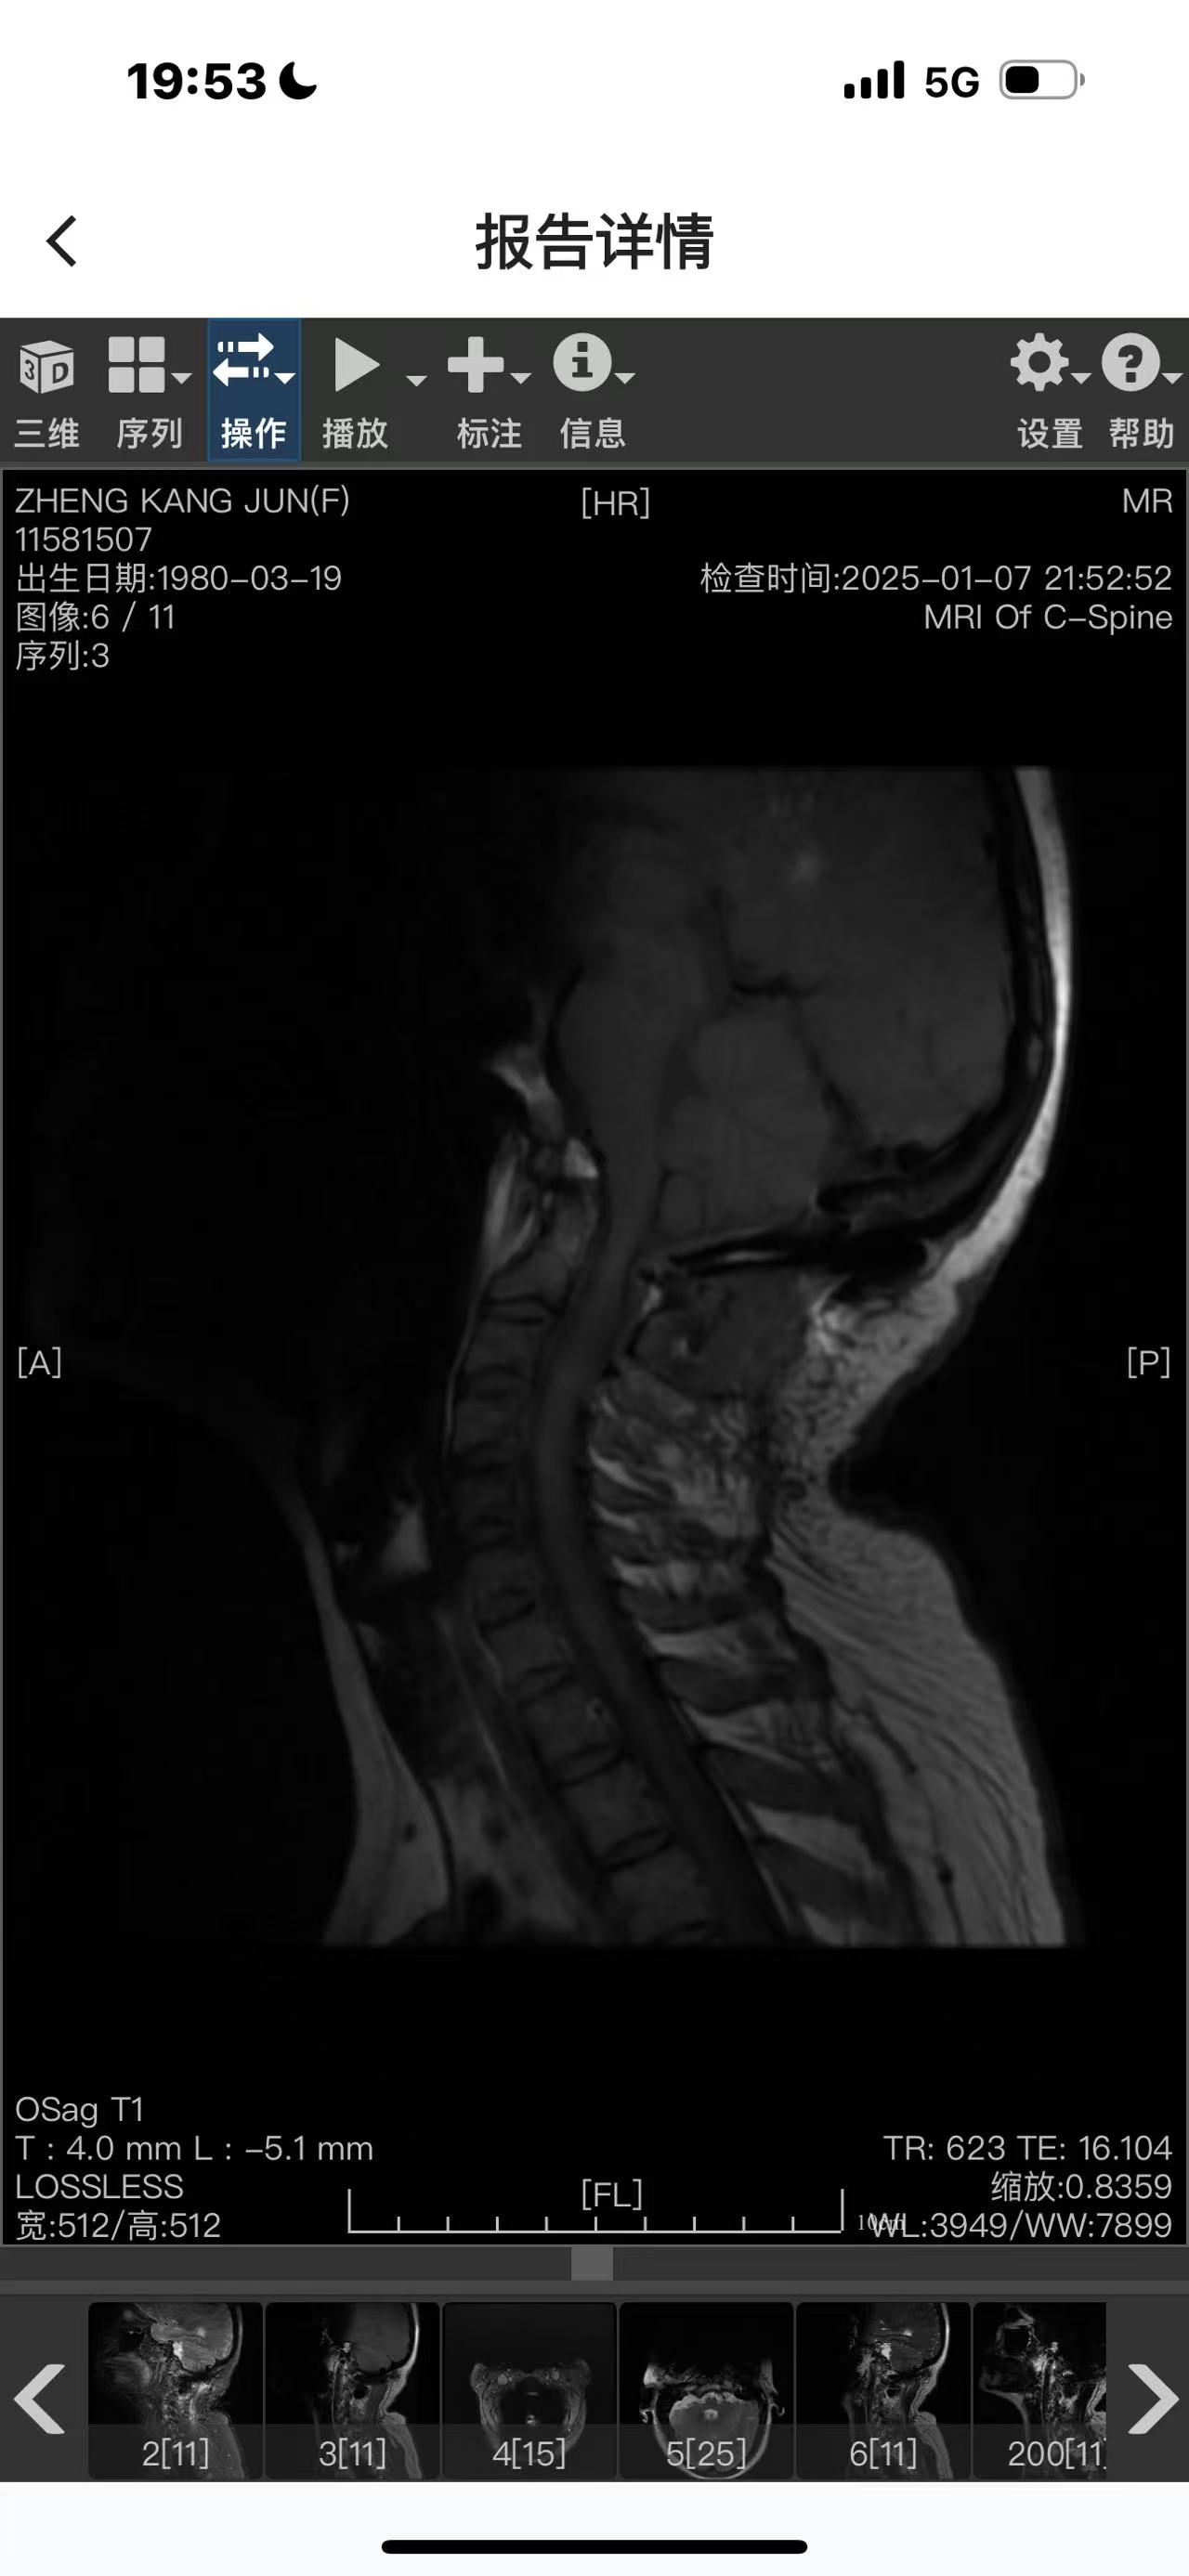

• 诊断:寰枢椎脱位

• 术后影像: